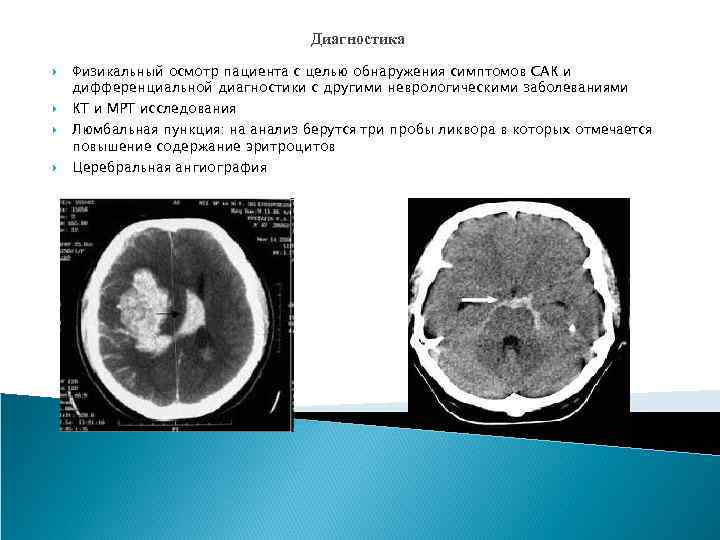

Диагностика Физикальный осмотр пациента с целью обнаружения симптомов САК и дифференциальной диагностики с другими неврологическими заболеваниями КТ и МРТ исследования Люмбальная пункция: на анализ берутся три пробы ликвора в которых отмечается повышение содержание эритроцитов Церебральная ангиография